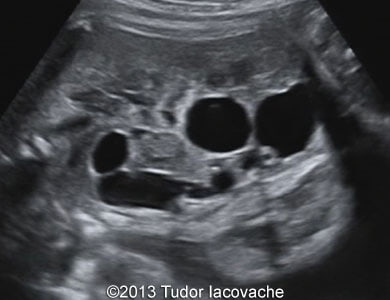

The patient was a 28-year-old primigravida. Fetal hydronephrosis with dilated renal pelvis and calices of the left kidney was noticed at 17 weeks. At 23 weeks the left kidney showed signs of multicystic dysplasia - the enlarged kidney consisted of isolated multiple cysts of various sizes. At 29 weeks the finding was even more striking. The right kidney was normal throughout the pregnancy. The multicystic dysplastic kidney was confirmed after birth.

Image 3 and video 2: 23 wekks of gestation.